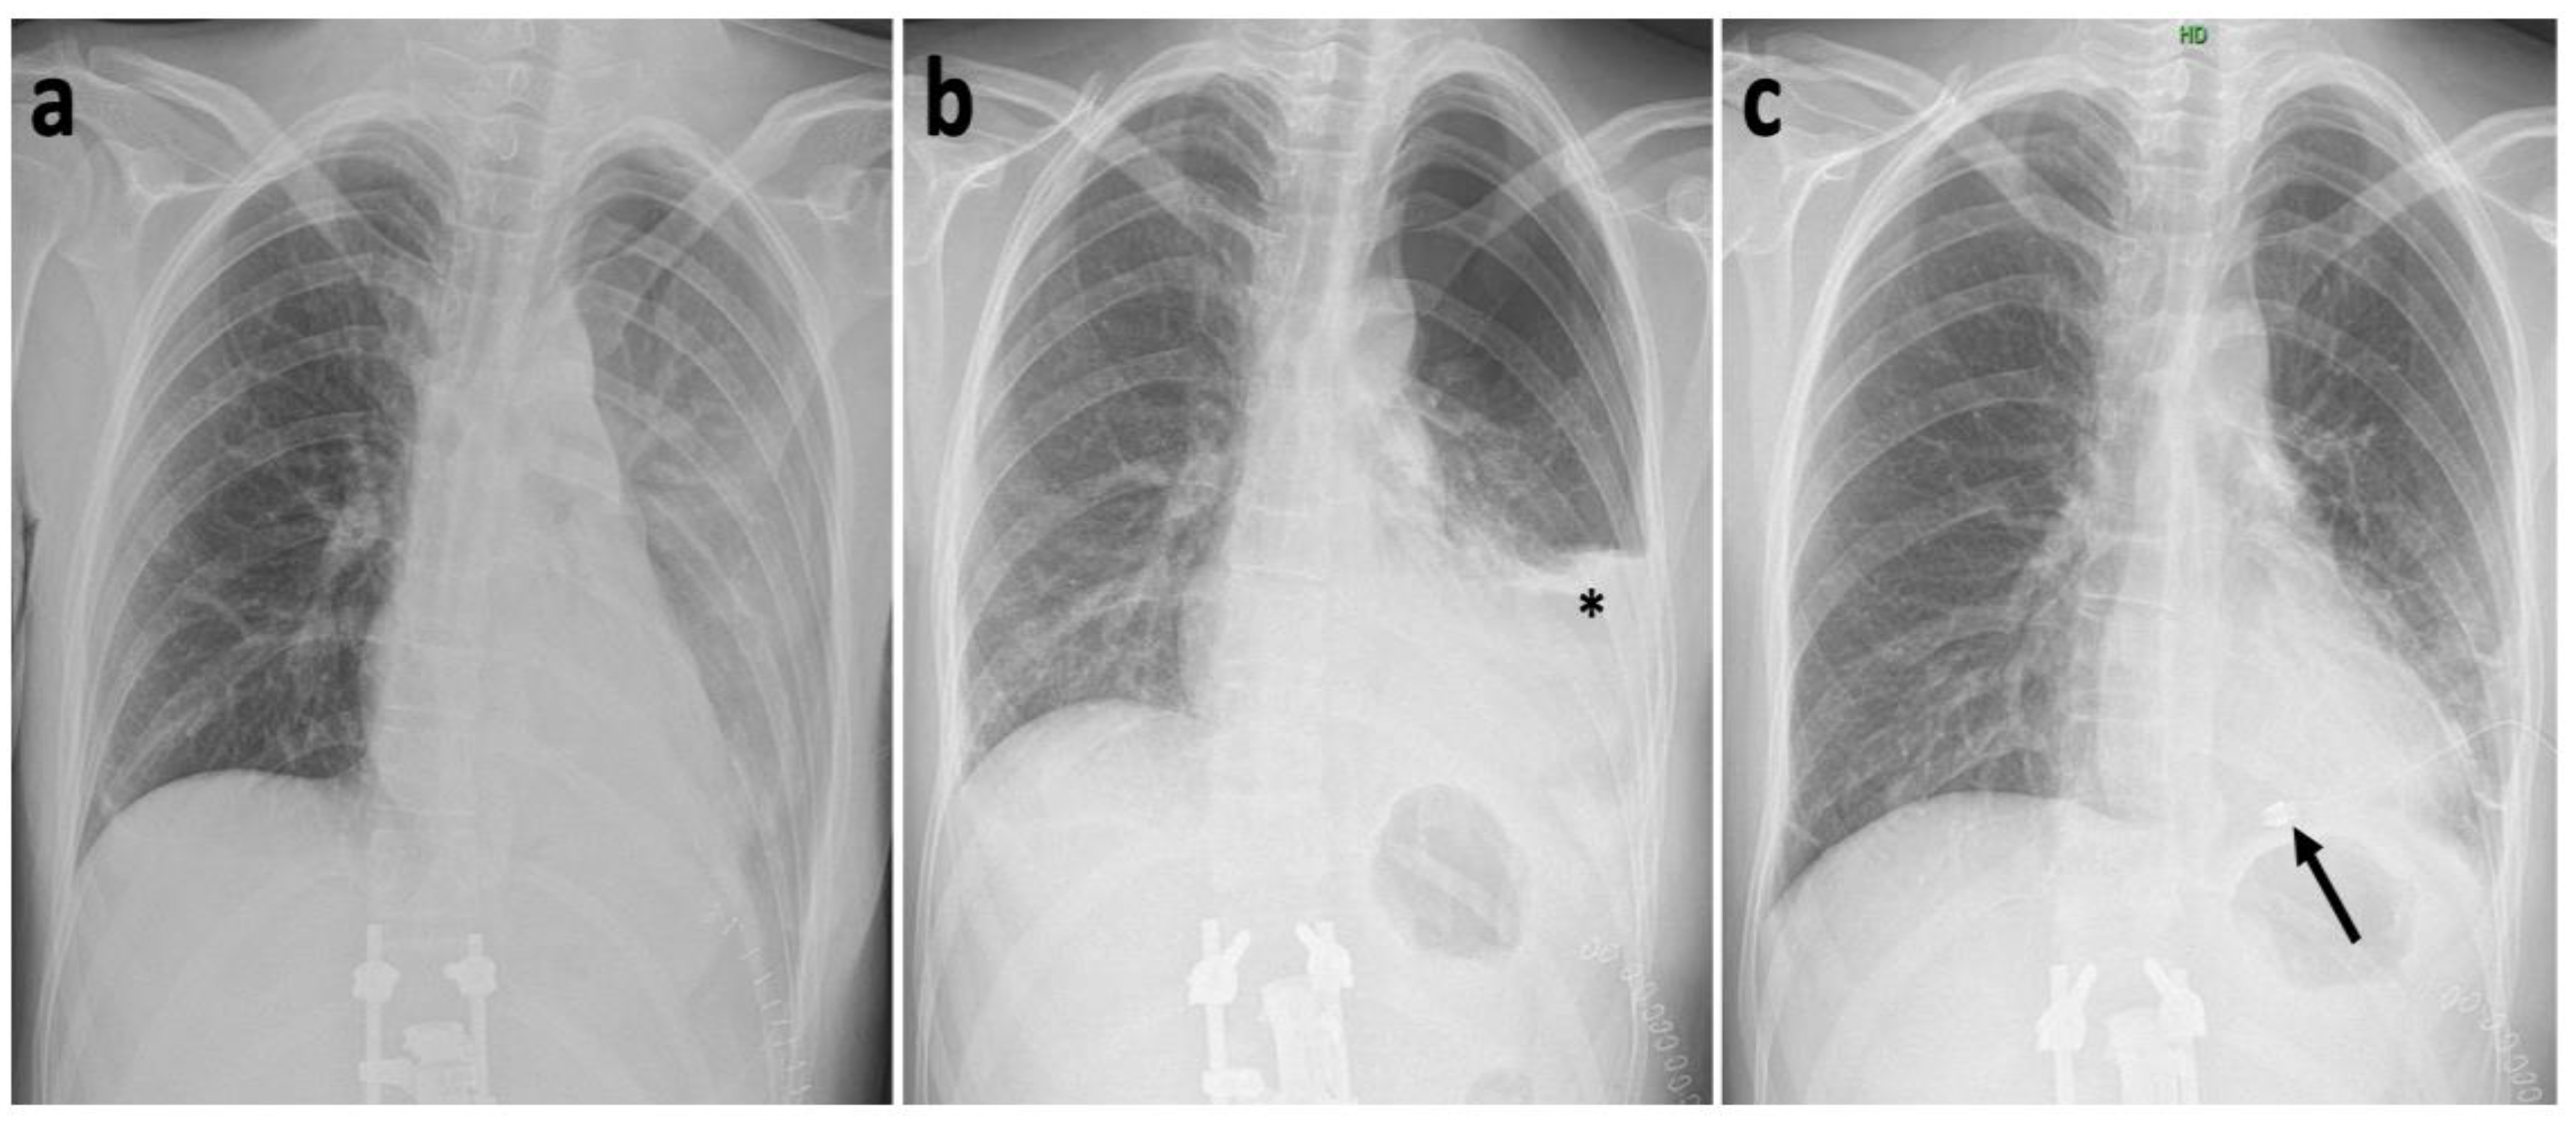

2. Case History